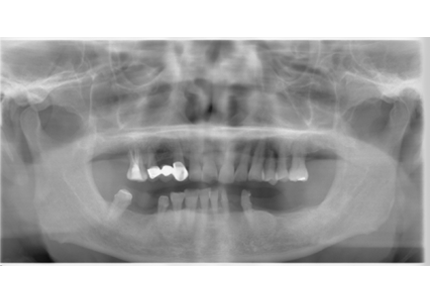

1.初診時(2015年6月)

2.最終補填物装着(2018年3月)

3.術後8年経過(2023年3月)

術後8年経過良好

2015年6月初診時レントゲン

2023年3月レントゲン 経過良好